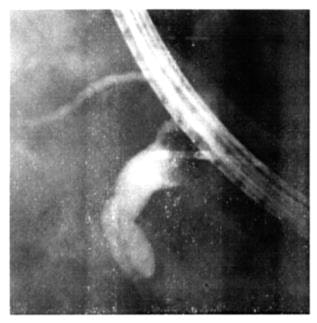

На фигуре 3:

фиг. 3

рентгенограмма «внепечёночных жёлчных протоков» и правого «внутрипечёночного протока» (выполненных предложенным «Способом рентгенологической визуализации …»).

На фигуре 4:

фиг. 4

рентгенограмма правого «внутрипечёночного протока», «внепечёночных жёлчных протоков» и поступление контраста в «двенадцатиперстную кишку».